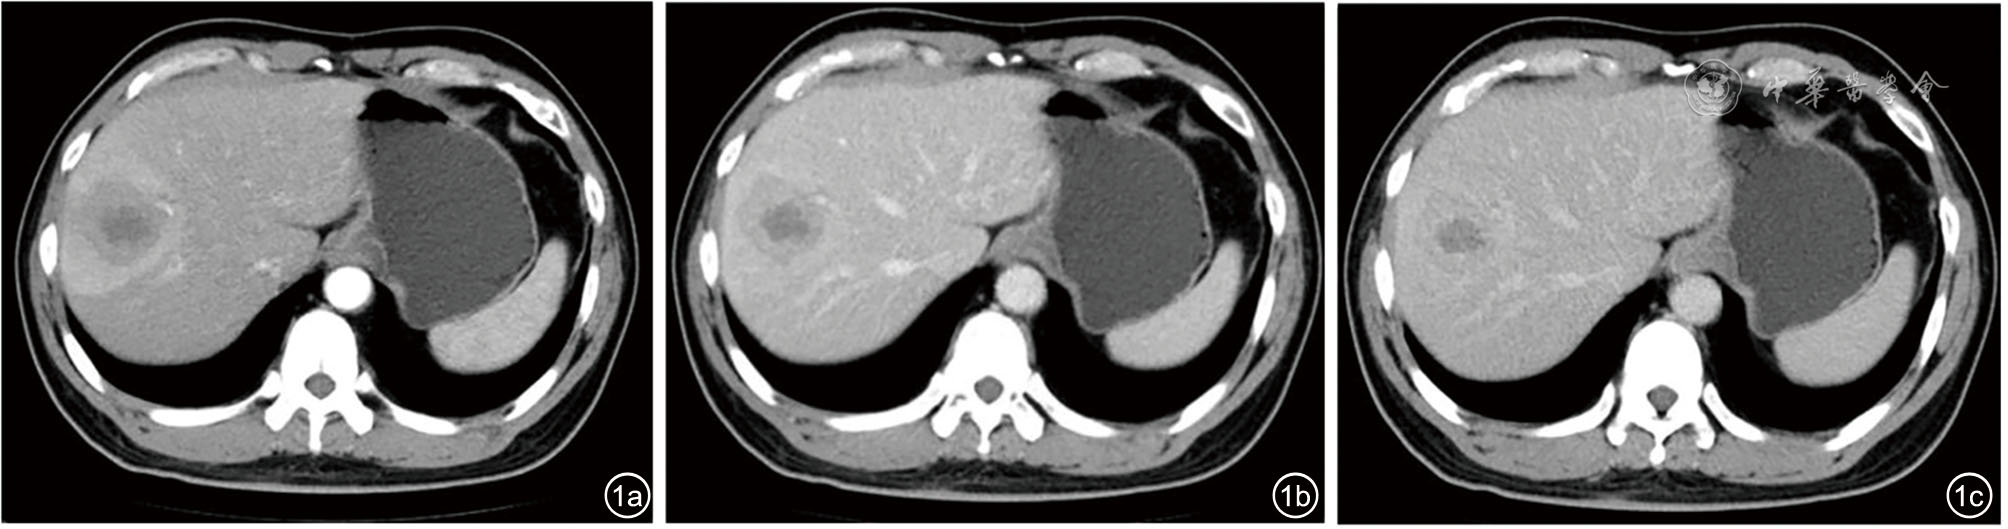

患者男性,42岁,右下腹酸胀疼痛3个月,无发热、寒战、周身黄染等其他症状,无肝炎病史。深圳市人民医院门诊CT检查发现肝右叶一类圆形低密度影,边界欠清楚,大小约4.5 cm×4.2 cm,增强扫描呈填充式强化,内壁欠光整,病灶内见小片状无增强区,动脉期病变周围见异常灌注(图1)。CT提示:肝右叶占位,考虑肝脓肿可能性大,肿瘤性病变待排查。实验室检查:直接胆红素浓度为8.5 μmol/L,总胆红素浓度为30.7 μmol/L,丙氨酸氨基转移酶40.1 U/L,碱性磷酸酶125 U/L,其余指标均在正常范围内。中性粒细胞比值、中性粒细胞绝对值在正常范围内,肿瘤标志物癌胚抗原、甲胎蛋白、糖类抗原199均阴性。入院行抗感染治疗1周后复查超声:肝右前、后叶交界处可见一大小约4.9 cm×4.6 cm实质性团块,形状欠规则,内部为不均质低回声,边界尚清楚,无声晕,彩色多普勒血流成像见团块周边较丰富血流信号,内部见少量血流信号。超声造影:经肘静脉团注造影剂2.4 ml,14 s肿块周边实质呈快速不均匀增强;24 s达峰值,中央可见无增强区,范围2.6 cm×1.5 cm;于门脉期早于周边实质开始消退,延迟期进一步消退(图2);结合超声造影提示:考虑肝细胞癌可能,肝脓肿待排查。进一步行磁共振造影检查:肝右叶见大小4.9 cm×3.5 cm类圆形长T1稍长T2信号影,弥散明显受限,中央见小片状长T1短T2区域,中央区域弥散未见受限,增强扫描病灶各期呈环形强化,中央未见明显强化,肝胆期未见明显造影剂摄取(图3),诊断:考虑肝脓肿,纤维板层样肝癌待排查。此后1周内多次复查腹部超声,均提示肝占位病变无明显变化,临床排除肝脓肿可能,考虑肝细胞癌可能性大。遂行机器人辅助腔镜下肝S8段切除术。常规病理:肿瘤大小4.0 cm×4.0 cm×3.5 cm,与周围肝组织界限尚清楚,在大量淋巴细胞、浆细胞、组织细胞及多核巨细胞的背景下,见梭形滤泡树突样或纤维母细胞样细胞呈条束状分布,核空泡状、核仁明显,可见多灶性坏死;免疫组织化学检测结果显示肿瘤细胞CD21(+)、CD23(+)、CD35(+)、SSTR2(+)、SMA(-)、CD3(-)、CD20(-)、CD138(浆细胞+)、Ki-67(20%+)、IgG4/IgG(<40%);原位杂交结果:EB病毒(Epstein-Barr virus,EBV)壳抗原IgA抗体阳性[EBV脱核RNA(Epstein-Barr virus enucleated RNA,EBER)+]。最终病理诊断为EBV阳性炎性滤泡树突细胞肉瘤(EBV+ inflammatory follicular dentritic cell sarcoma,EBV+IFDCS)。术后未进行放化疗,随访16个月未见肿瘤复发及转移。

图1 肝病灶增强CT呈填充式强化,内壁欠光整,可见小片状无增强区。图a为动脉期,图b为门脉期,图c为延迟期